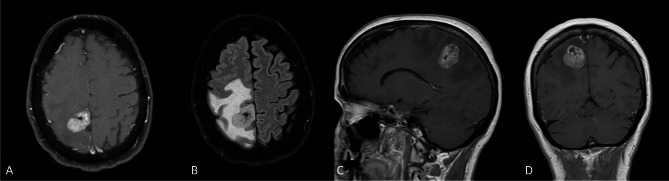

Results: Three patients were identified: two females and one male with a mean age of 49.7 years (range 25-62). No patients had a prior cancer history. One patient had an incidentally discovered tumor, while the other two patients underwent imaging for symptoms of headache, vision changes and extremity weakness. Mean tumor size was 4.0 cm (range 2.8-6) with a wide variation in imaging characteristics. All patients underwent surgical resection and radiographic gross total resection was achieved in all cases. All patients underwent radiation therapy without concurrent chemotherapy. After a median 20 months follow up (range 4.5 to 108.9), two patients experienced tumor progression at 2.7 months and 86.5 months respectively. All patients were alive at last follow up.